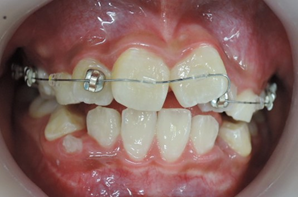

上顎から矯正装置を装着していきます。

上顎の歯が揃ってから、下額に矯正装置(ブラケット)を装着します。

初診時

初診時より1年6カ月後 終了時(10歳9か月)

初診時より2年2カ月後

上下顎骨も拡大でき、咬み合わせの高さも改善できました。

今後、永久歯が萌出してから歯列矯正治療によってさらに美しい咬み合わせに改善していく事となります。